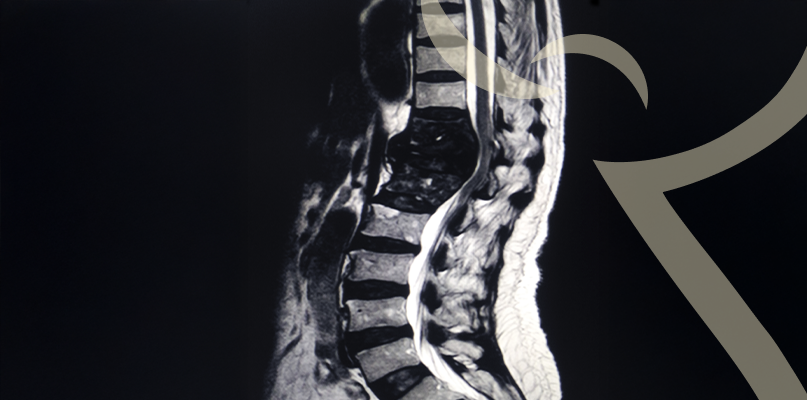

Tumores na Coluna – diagnóstico precoce faz a diferença

Os tumores da coluna podem ser benignos ou malignos, atingindo ossos, medula ou nervos.

Depende do tipo e localização do tumor, podendo incluir cirurgia, radioterapia e quimioterapia. O objetivo principal é preservar a função neurológica e a qualidade de vida.